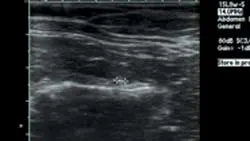

ImagingAbdominal radiographs showed small irregular kidneys (Figure 1, right: Radiograph of the right lateral abdomen. The kidneys are small and irregularly shaped. Mineral densities are visible in the left kidney. View larger image), and irregular margins were evident in ultrasound imaging (Figure 2, below: Ultrasound of the left kidney demonstrating irregular margins. View larger image).